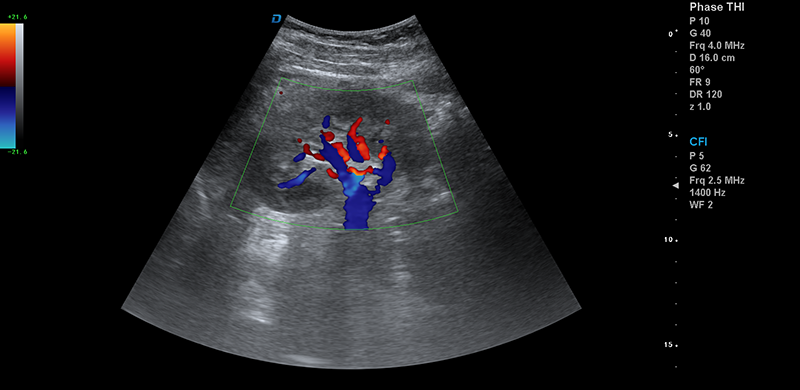

頸動脈血流